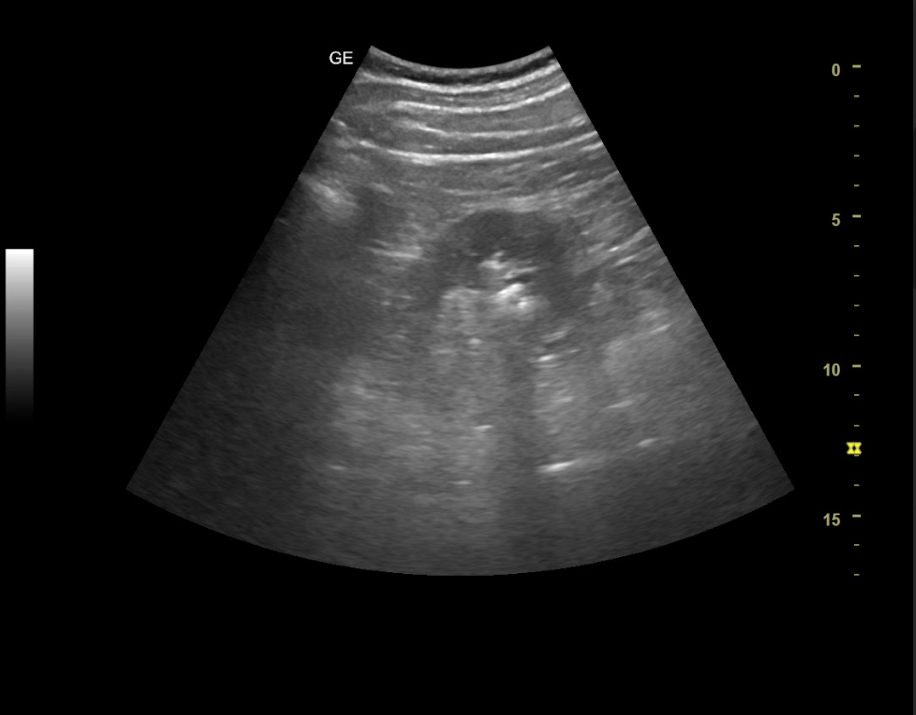

Hallazgos ecográficos

Ambos riñones son de tamaño similar considerándose normales y no apreciando hidronefrosis asociada. En el interior del riñón derecho se aprecia litiasis renal única que proyecta sombra posterior de diámetro máximo de 8,68 mm y potencial responsable del cuadro.